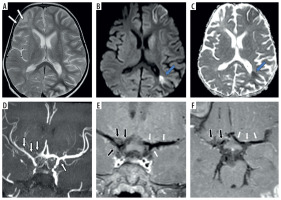

Figure 3

Three-year-old female presenting with right sided hemiparesis for 2 months with recurrent right focal seizures. Axial T2 (A), axial diffusion-weighted imaging (B) and axial apparent diffusion coefficient map (C) images show volume loss in right fronto-parietal region (white arrows in A) with a few foci of diffusion restriction in left parieto-temporal region with cortical diffusion restriction in left frontal lobe (blue arrows in B and C). Coronal anterior view maximum intensity projection time-of-flight magnetic resonance angiography (MRA) image (D) shows stenotic right supraclinoid internal carotid artery (ICA), right terminus ICA, right anterior cerebral artery (ACA) and right middle cerebral artery (MCA) and also left supraclinoid ICA (white arrows in D). Coronal oblique post-contrast vessel wall imaging (VWI) (E) and axial post-contrast VWI (F) showing vessel wall thickening and grade 1 concentric enhancement of right supraclinoid, terminus ICA, right MCA and ACA (black arrows in E and F). Grade 1 concentric enhancement is also noted in left supraclinoid, terminus ICA and left MCA and ACA (white arrows in E and F)